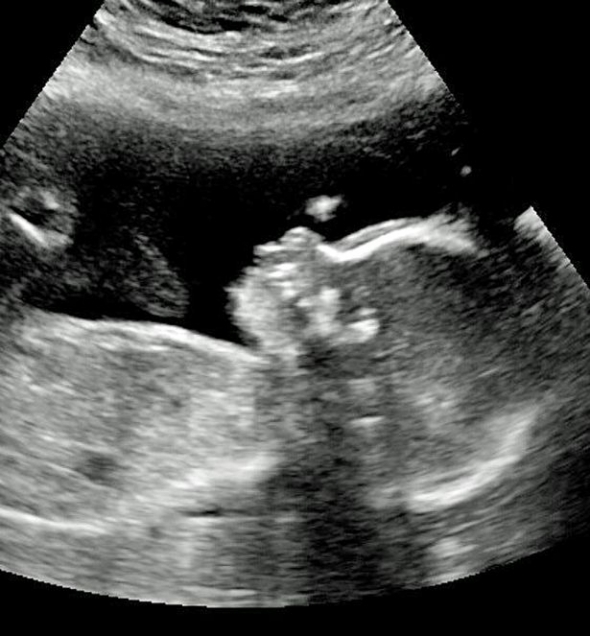

В американської пари Енджі та Браяна Данн народився малюк із довгим волоссям на голові. Біляві пасма ще ненародженого Олівера бачили на ультразвуковому скануванні.